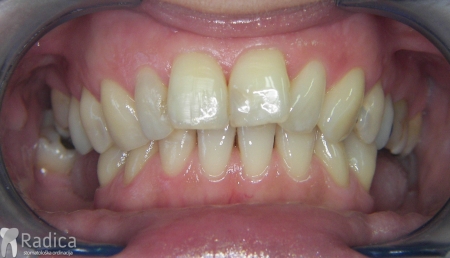

Ortodontska terapija ispravlja položaj zuba i pomaže da bolest dalje ne napreduje. Normalno, kako se ortodontska sila prenosi na onaj dio korijena koji je u kosti, u ovim slučajevima treba biti oprezniji i koristiti slabije sile, pojačavati sidrišne zube itd. Nakon terapije obavezno se stavlja fiksni retainer i potrebno je protetski nadoknaditi zube koji nedostaju.

Prosječni gubitak visine kosti uslijed ortodontske terapije je od 0,5-1 mm, najviše u području ekstrakcijskih mjesta. Ekscesivni gubitak visine kost se gotovo nikad ne viđa kao posljedica ortodontske terapije. Izuzetak je pomak zuba kada postoji aktivni paradontitis. U tom slučaju pacijent se šalje našem suradniku specijalistu paradontologije dr. Dariu Bojčiću na inicijalnu parodontološku terapiju. Tek kada se parodont dovede u stanje bez aktivne upale, započinje se ortodontska terapija i pacijent odlazi na kontrolne preglede parodontologa.

U galeriji slika su prikazani klinički slučajevi ovakvih odraslih pacijenta bilo da se radi samo o ortodontskoj terapiji ili predprotetskoj ortodonciji.